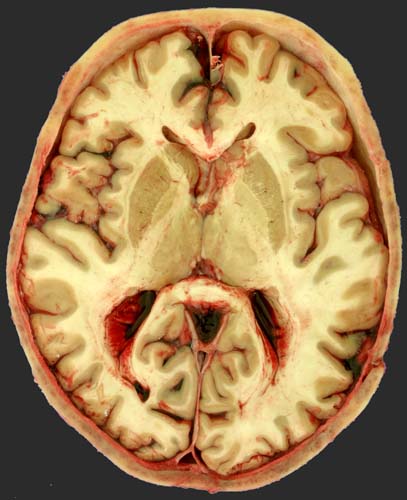

Обстоятельства: Пожилой мужчина находясь судя по описаниям двух свидетелей (оба тоже пьяные) в сильной стадии алкогольного опьянения шёл неуверенно, сильно покачиваясь и толкая рядом с собой велосипед, т.к. ехать на нём похоже не мог. Был потерян свидетелями из вида. Шёл к ж/д путям. При попытке пересечь ж/д пути попадает под товарняк, который двигается со скоростью 20-25 км/ч. Машинист тепловоза говорит, что солнце стояло так низко, что он из-за ослепления только непосредственно перед столкновением велосипед заметил. Пострадавшего вообще не видел. Экстренно затормозил, тут же вызвал "органы", те сразу "скорую". Пострадавшего обнаружили рядом с путями в кустах, в 1-2 метрах от рельса. Велосипед покарёжен и лежит на полотне. Голова потерпевшего лежала якобы на бетонном камне или блоке, который лежал в кустах. Минут через 10 приехал врач скорой помощи, потерпевшего вытащили из кустов, он был ужё мертв.

На вскрытии (примерно 12 часов после обнаружения): Одежда вся разрезана и запачкана кровью. Труп полностью раздет. Трупное окоченение резко выражено. Трупные пятна на задней поверхности, скудные. Признаков гниения нет. Повреждений на теле за исключением головы вообще никаких нет. В левой височной области с переходом на теменную ушибленная рана длиной 5 см с частичным рассечением ушной раковины. В глубине пальпируются кости. В области правой надбровной дуги несколько поверхностных свежих царапин.

Внутреннее исследование: Туловище, шея, конечности абсолютно чистые, без единого повреждения! Черепно-мозговая травма (см. фото). От линейного максимум на 0,3 см вдавленного перелома на границе чешуи левой височной кости (в задней трети, идёт сверху-вниз, сзади-наперёд), который соответствовал ране на коже, отходят трещины и на основание черепа, где видны пероломы левой, правой основной кости и турецкого седла. Твёрдая мозговая оболочка без разрывов. Субдурально крови практически нет. Субарахноидально минимальные кровоизлияния (см. фото) в области удара и противоудара. Признаков сдавления, отёка гол. мозга нет. Ушибов не видно. Единственно, что обращает на себя внимание это смесь крови с ликвором в боковых желудочках, но не очень много.

Умер вроде бы от черепно-мозговой травмы. Ничего другого-то нет! Правда сильный запах алкоголя, но это вроде так себе.. попутно.

Вот представьте себе, что стою теперь рядом с трупом и тереблю бороду. Вскрытие закончено, а от чего хоронить? Ну понятно, что ЧМТ напишу, но самому не понятно отчего же он умер?

Как вы думаете достаточно ли этих повреждений чтобы его от ЧМТ "похоронить"? И от каких конкретно повреждений он вероянее всего умер?